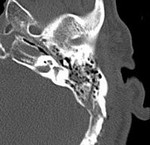

[画像診断]膵管走行および膵管の解剖学的異常(膵管癒合不全=divisumを含めて) 2010-08-13